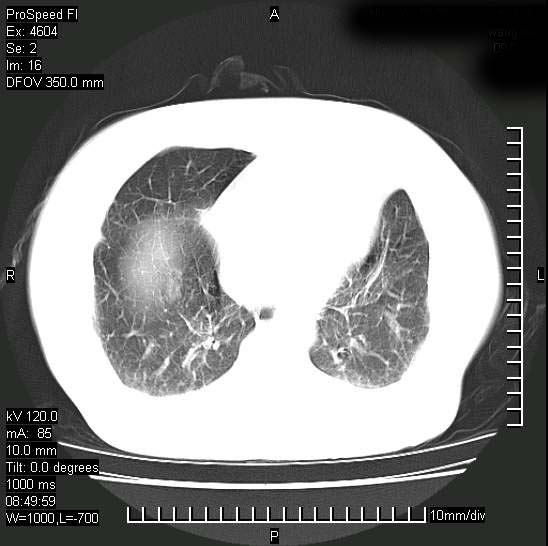

十几年前曾患肺结核,一周前突咳血约100ml,中性粒细胞稍高,诊断两上肺陈旧结核,下肺炎症,给予抗炎治疗,近几日晚上高热,39度,仍咳少量血,4天前ct及今天ct上传。

[face=黑体]8月30日[/face]

支持陈旧性肺结核并两下肺感染,两侧胸腔积液。

考虑1双肺tb灶;右下肺支气管壁增后,建议除外占位 3双侧胸腔积液,

短短几天内,病变范围明显增多扩大,以左侧明显,而且双侧出现胸水,还是考虑感染.

支持  结核ban感染,节段性肺不张,支气管内膜结核可能

短短几天内,病变范围明显增多扩大,以左侧明显,而且双侧出现胸水,我更多考虑左侧中心性肺癌并并阻塞性不张及肺炎,炎症变化也太快了!

继发性结核感染加重。左侧合并有支气管内膜结核。

无论是肿瘤还是炎症4天的时间都发展够快的,并且还在治疗中,如果说是左肺癌那么右肺的病变不好解释,本人更加倾向于炎症,左肺舌叶支气管被痰栓或血凝块堵塞,造成阻塞性肺炎。

1)两肺结核并感染。2)不排除左肺上叶中央型肺癌并阻塞性肺炎、肺不张可能;建议行纤支镜检查。3)右肺门及纵隔淋巴结肿大。4)双侧胸腔积液。

陈旧性肺结核及左下肺不张,咯血后肺部感染,双胸腔积液,高热可能与痰液引流不畅有关。